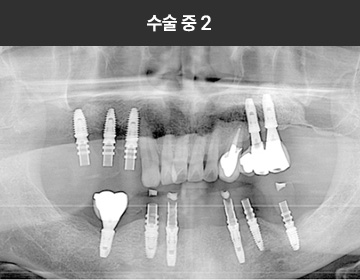

BMP를 이용한 수술 사례      I

치료 기간 : 2023.03.22 ~ 2023.09.15

* 상기 사례의 경우, 해당 의료기관에서 진료를 한 환자분의 동의를 얻어 사용되었습니다. * 치료 전후의 사진은 동일 인물과 동일한 조건에서 촬영 되었음을 알려드립니다.

* 모든 수술 및 시술은 개인에 따라 부작용고지 : 임플란트치료는 치료 후 감염,

염증, 연조직합병증, 출혈, 감각이상 등의 부작용이 있을 수 있습니다.

의료진과 충분히 상의 후 신중하게 결정하시기를 바라겠습니다.